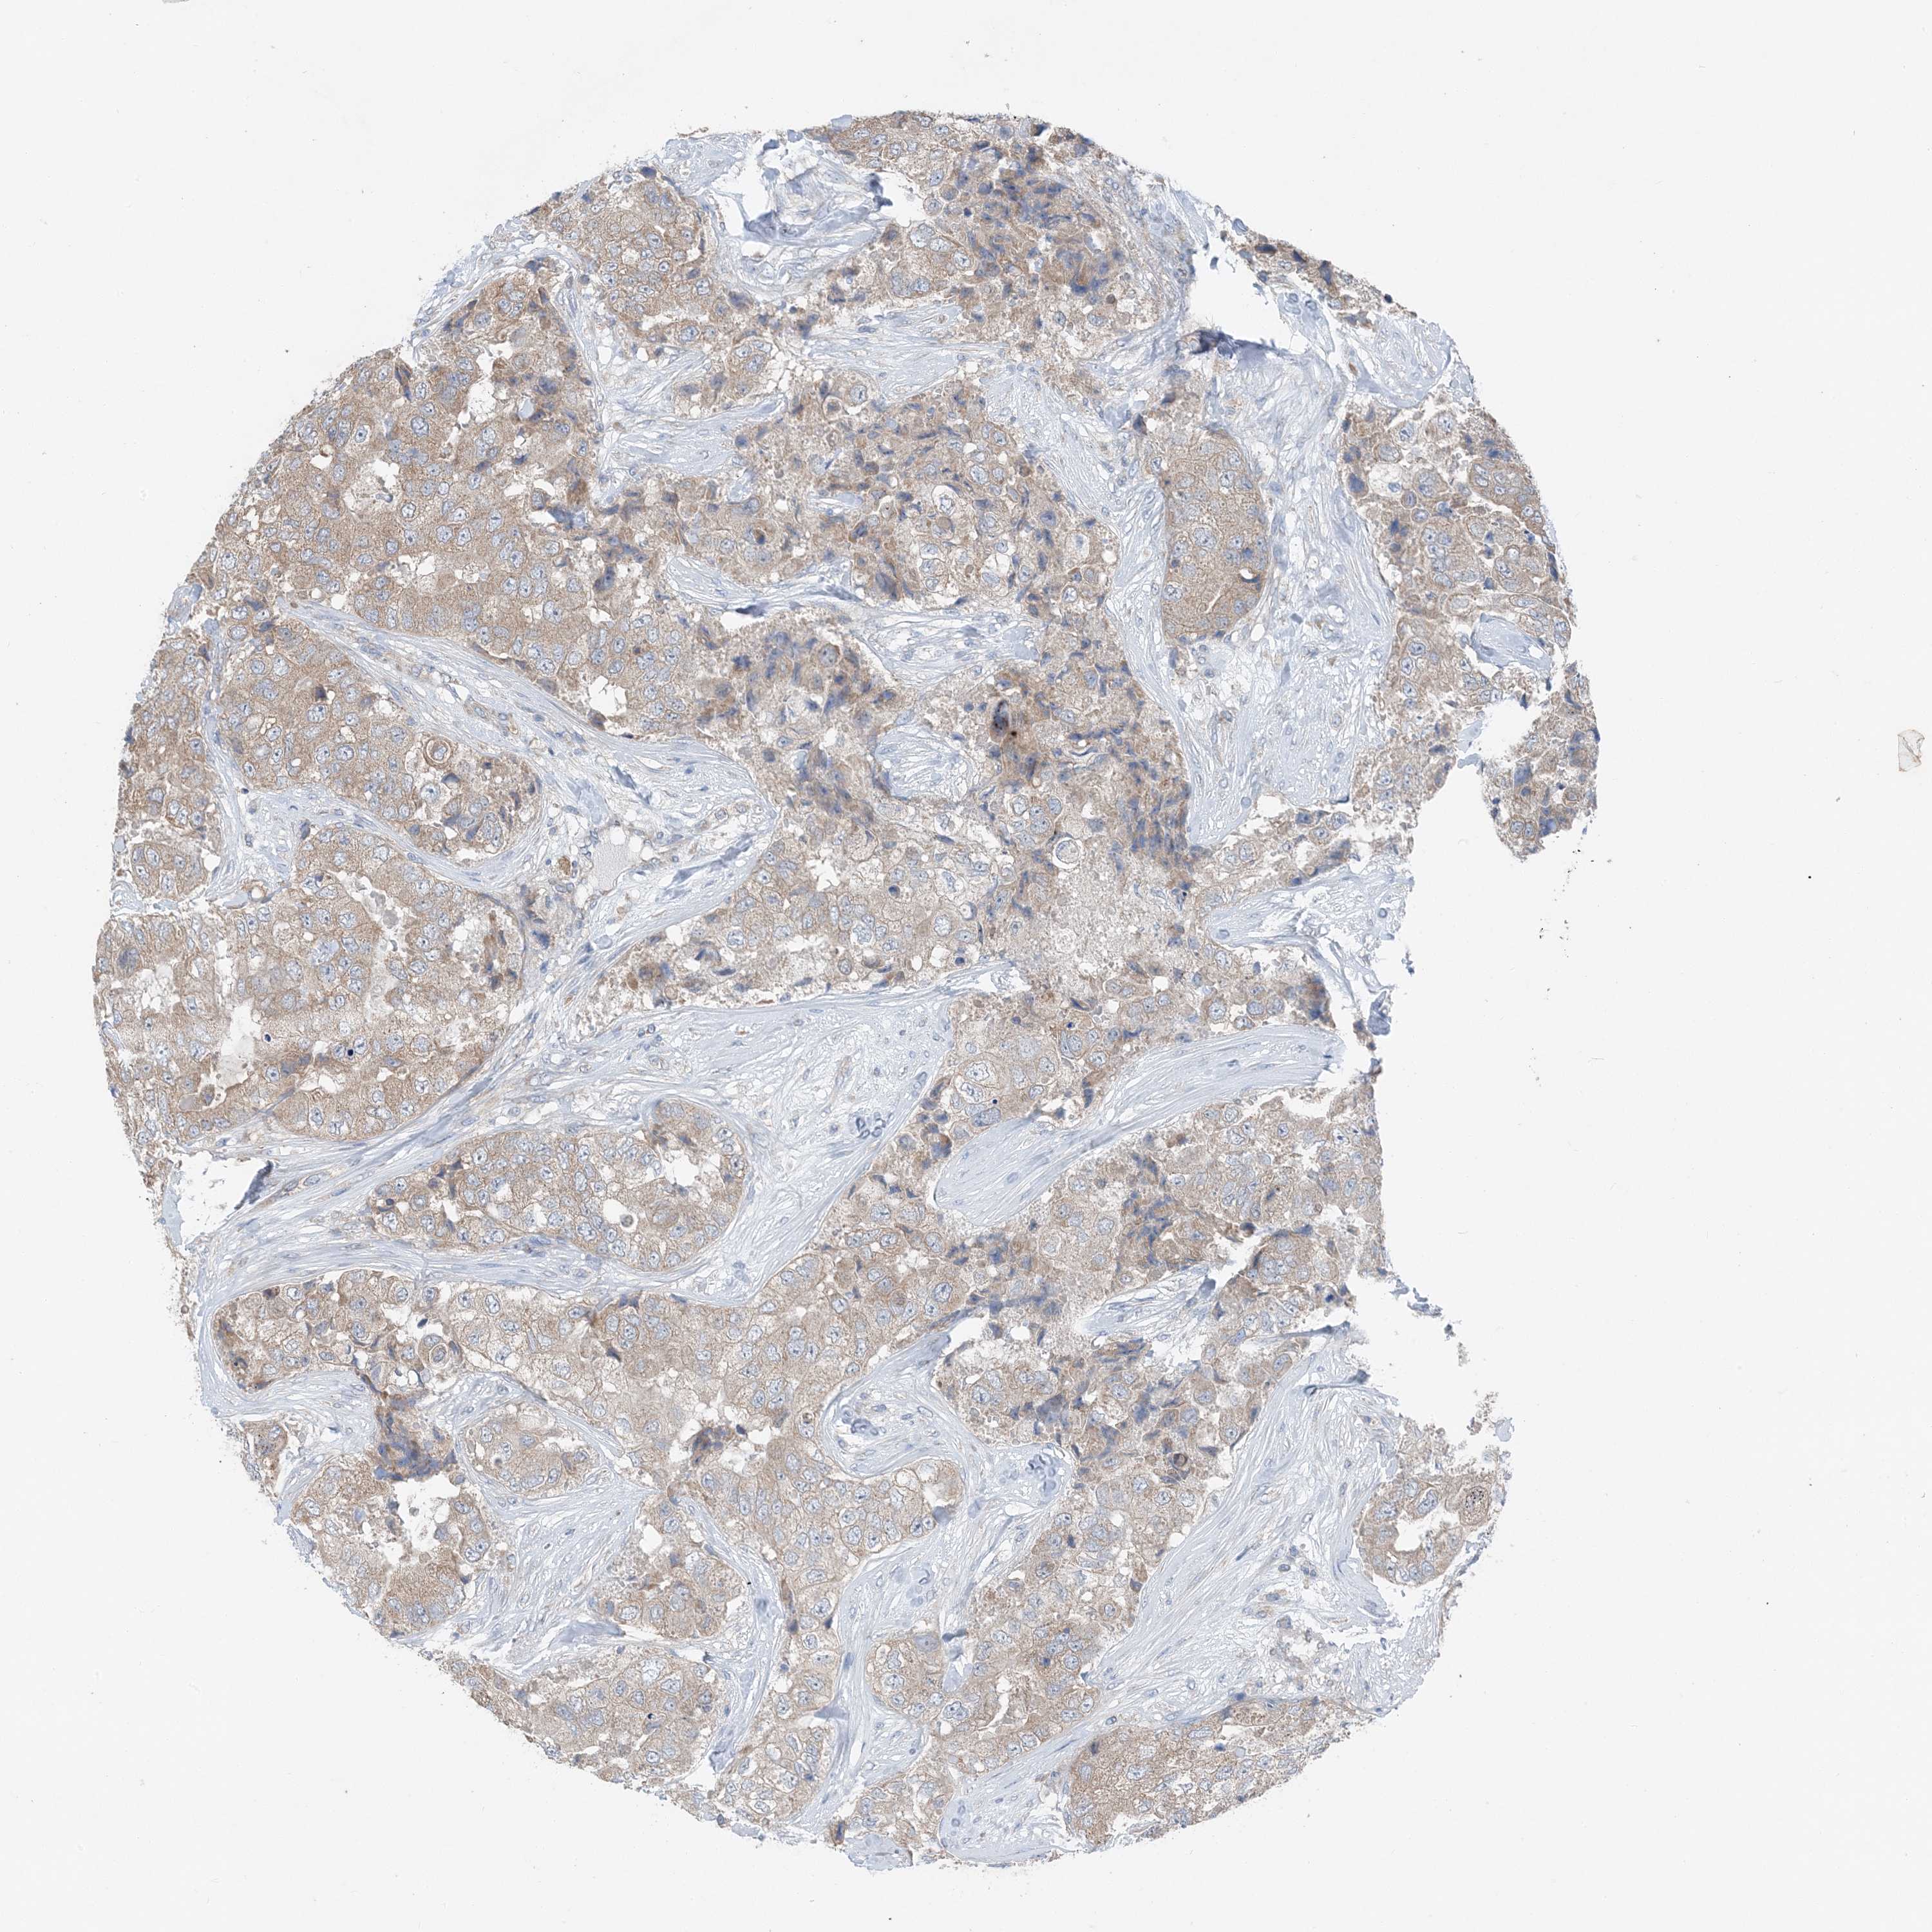

BRCA TCGA BRCA VALIDATION PROTEIN EXPRESSION

ANTIBODIES

AND

VALIDATION